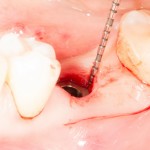

Лунка готова:

В данном случае мы используем XiVE, что, с одной стороны, несколько сложнее, чем, к примеру, использование погружного импланта, но, с другой — позволяет нам ориентироваться по абатменту TempBase, который входит в комплект поставки и является, одновременно, имплантодержателем:

Временный абатмент/имплантодержатель помогает понять, какую картинку увидит врач-ортопед перед началом протезирования. ИМХО, это очень удобно.